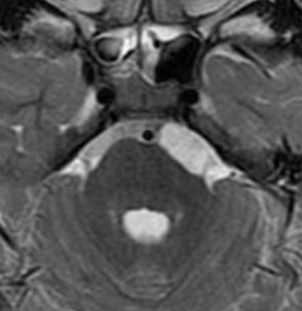

Киста кармана Ратке представляет собой редко встречающееся образование из остатков эмбриональной эктодермы (щель Ратке), расположенное между долями гипофиза. Выявляется в любом возрасте, но чаще в 50-60 лет. Клинические проявления связаны с масс-эффектом. При головного мозга выявляется небольшая (3-5 мм) киста с четким контуром, без отека вокруг, однородная по структуре. Сигнал зависит от содержимого. При серозном содержимом сигнал типично жидкостный, при мукоидном киста светлая на Т1-взвешенных МРТ. В редких случаях киста достигает больших размеров и даже выходит за пределы седла. Стенка кисты иногда усиливается при контрастировании.

МРТ головного мозга. Т2-взвешенная корональная МРТ. Киста кармана Ратке.

Киста кармана Ратке представляет собой редко встречающееся образование из остатков эмбриональной эктодермы (щель Ратке), расположенное между долями гипофиза. Выявляется в любом возрасте, но чаще в 50-60 лет. Клинические проявления связаны с масс-эффектом. При МРТ головного мозга выявляется небольшая (3-5мм) киста с четким контуром, без отека вокруг, однородная по структуре. Сигнал на МРТ головного мозга зависит от содержимого. При серозном содержимом сигнал типично жидкостный, при мукоидном киста светлая на Т1-взвешенных МРТ головного мозга. В 70-80% случаев внутри кисты выявляется неконирастирующийся узелок («пятно») - признак патогномоничный для кисты кармана Ратке. В редких случаях киста достигает больших размеров и даже выходит за пределы седла. Стенка кисты иногда усиливается при МРТ головного мозга с контрастированием. Дифференциальная диагностика при МРТ головного мозга должна проводиться с арахноидадьной и эпидермоидной кистами, тератомой, кистозной аденомой гипофиза и краниофарингиомой. Иногда при МРТ головного мозга киста кармана Ратке напоминает “пустое” турецкое седло. При маленьких размерах кисты ее на до дифференцировать на МРТ с микроаденомой гипофиза.